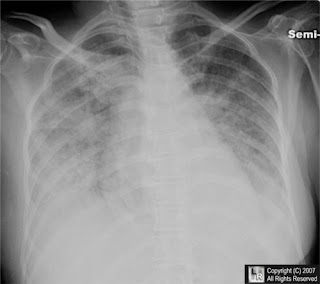

1-1,Right lung. 2, Left lung. 3, Right ventricle. 4, Left ventricle. 5, Inferior vena cava. 6, Descending aorta. 7, Thoracic spine. 8, Rib. 9, Hepatic dome